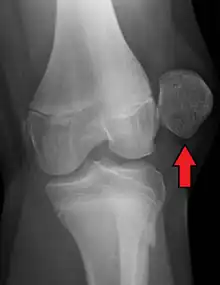

![]() | |

| X-ray showing a patellar dislocation, with the patella out to the side. | |